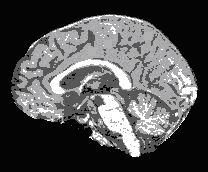

The left image in Figure 1 shows a segmented image that results after applying the C-means classification algorithm to a brain image produced with the brain extraction tool. The image on the right shows the result of applying the Mode filtering algorithm with a 3 x 3 x 3 local neighborhood to the image on the left. Clearly, the image on the right has fewer small isolated classes than the image on the left.

Figure 1. Examples of (A) a segmented image and (B) the results of applying the Mode algorithm to the image